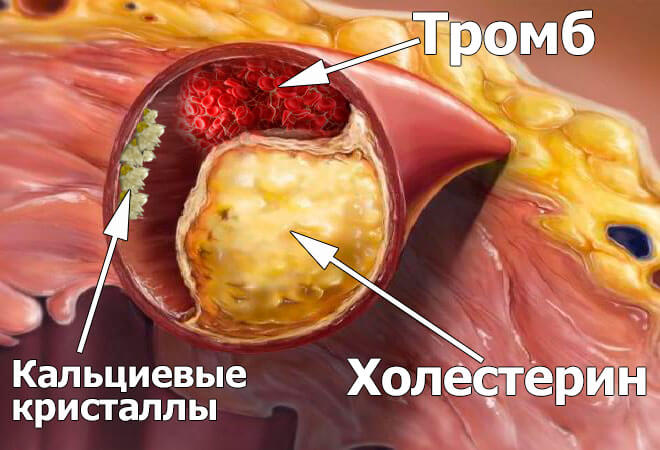

Так, ви маєте рацію. Холестеринові бляшки або як ще їх називають "атеросклеротичні бляшки" становлять приблизно 65-70% забруднень судин.

До 50-ти років у судинах людини накопичується до 5 кг холестеринових бляшок. Холестеринові відкладення звужують просвіт судин у 4-5 разів.

Уявіть. Якщо нормальний просвіт судини це ваш палець, то 5 кг холестеринових бляшок зменшує просвіт до розміру 4-х сірників.

Самі по собі холестеринові бляшки не становлять загрози життю. Так, якість життя падає, підвищується тиск, головні болі та болі в суглобах, слабкість і апатія. Набагато небезпечніша тромбова маса, яка теж накопичується в наших судинах.

Тромбів накопичується значно менше "всього" близько 800 грам - 1 кг. Але їх небезпека в тому, що вони нестабільні. У будь-який момент тромб (згусток крові) може відірватися і вирушити в подорож вашими судинами на пошуки жертви.

Якщо тромб досить великий, то він наглухо "запечатує" судину-жертву. Трапляється ішемія - повне припинення кровопостачання органу, що живиться цією судиною.

Ішемічний інсульт - закупорка судини мозку. Інфаркт - закупорка серцевої артерії. Ішемія печінки, колапс легені, відмова нирок. Геморой це ні що інше як ішемія судин прямої кишки. Закупорка навіть маленьких судин ніг, з часом призводить до некрозу - гангрени.

Кальцієве вапно в судинах - це залишки хімічних медикаментів і харчових добавок. Їх накопичується до 50-ти років грам 300-400. Найбільше вапна накопичується в судинах головного мозку.

Небезпека кальцієвого вапна в тому, що воно має гостру, кристалічну структуру. У разі різкого звуження - спазму судини, спричиненого стресом або фізичними навантаженнями чи погодою, гострий кристал вапна може проткнути судину і призвести до її розриву. А розрив судини головного мозку - це геморагічний інсульт.